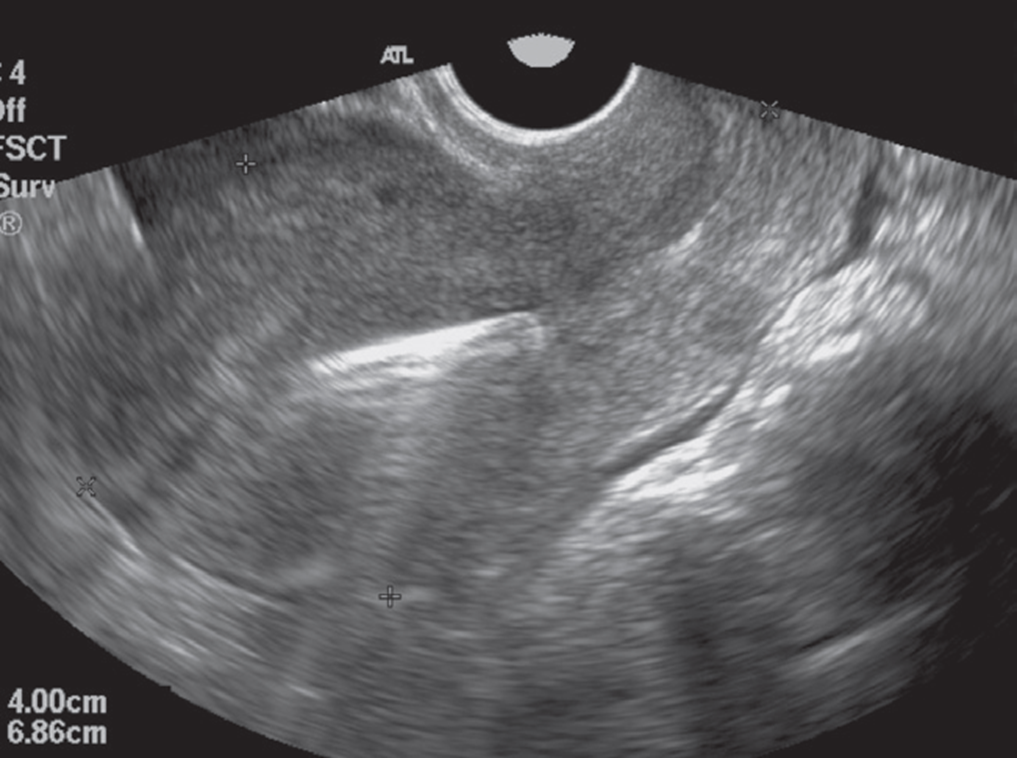

They are seen as highly reflective structures and their relationship to the uterine cavity can be determine.

Intrauterine contraceptive device seen as a linear reflective echo within the uterine cavity